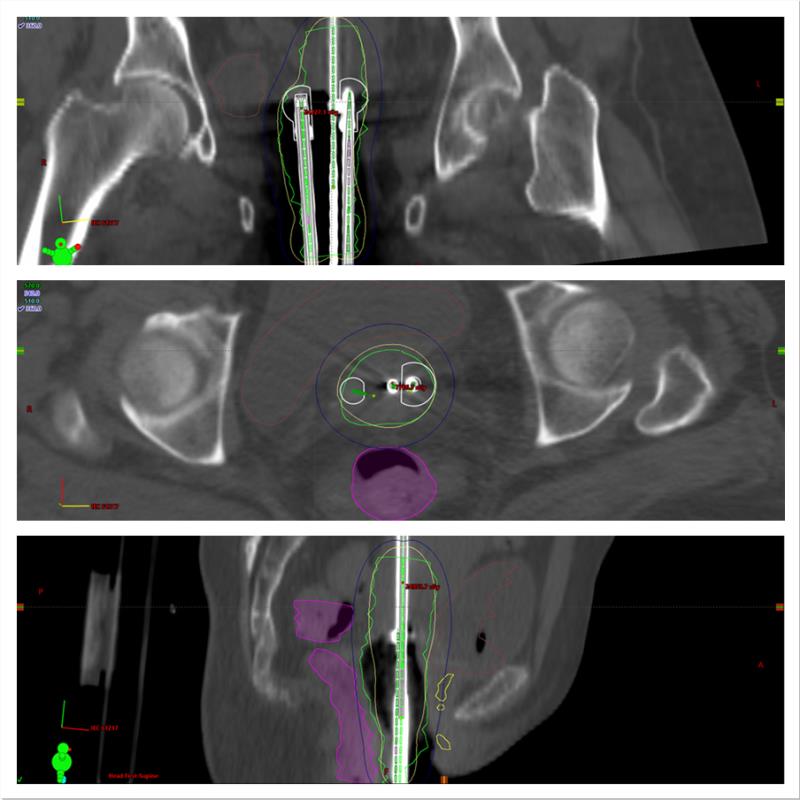

和外放疗一样,妇瘤后装治疗也逐渐进入三维精准放疗时代。和二维后装(依赖X线平片技术计算剂量并估测直肠和膀胱等正常组织剂量)相比,三维后装可依托CT以及MRI等影像技术融入,可在任一图像上直接勾画靶区和危及器官(直肠和膀胱等)并精确计算放疗剂量和覆盖范围,既保证疗效又能更可靠地保护正常组织。

我院购置的瓦里安3D后装机是目前国际上两大知名品牌之一,除了后装治疗外,还能开展另一行内放疗技术——插植治疗,针对后装治疗照射范围难以覆盖的较大或侵及范围较远的肿瘤,可直接将插植针穿刺进入瘤体补足该部位的照射剂量,同时能较好保护正常组织。不久我科将针对有需要的患者开展此项技术。另外,我院后装机机是瓦里安第五代近距离治疗机,具有以下特点:一、安全可靠:治疗距离固定大大减少了减少施源器和后装器连接相关的误差。并且后装机自带检测装置,可轻松验证施源器连接的完整性和治疗距离。二、全面整合共享同一数据库 ,与 BrachyVision治疗计划系统和 ARIA肿瘤信息系统的无缝连接,并且能够能够与外照射放疗计划进行剂量叠加,让肿瘤剂量及危及器官剂量更加精准.